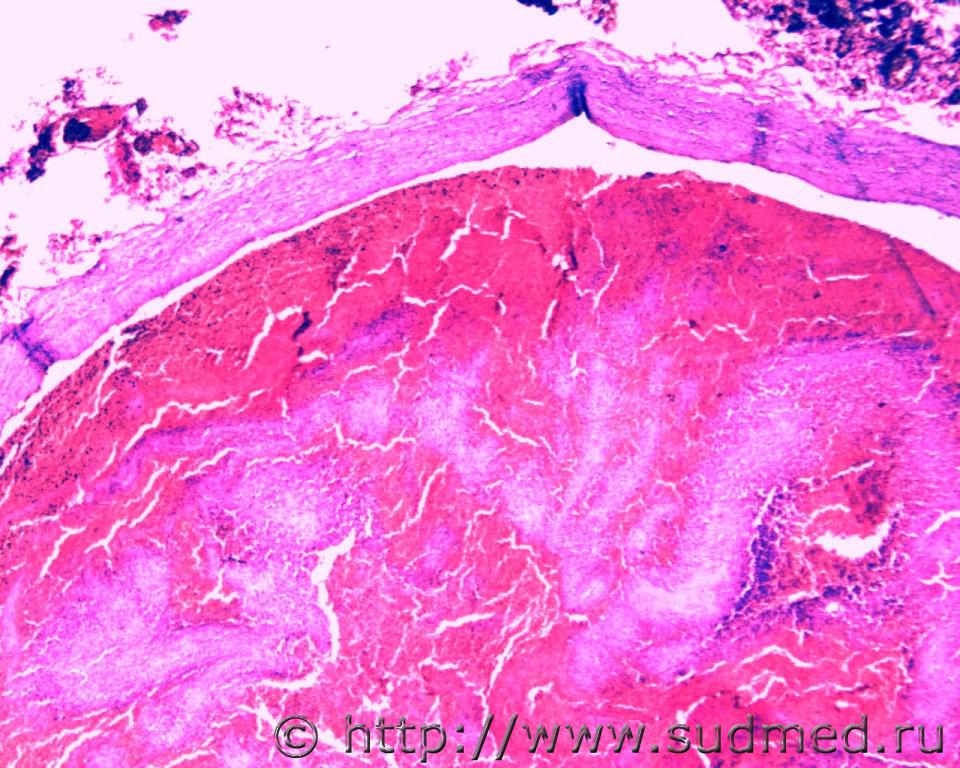

Тромбоэмболий легочных артерий.

1.Смешанный тромб в просвете мелкой ветви правой легочной артерии.

2.Геморрагический инфаркт лёгкого.